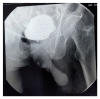

Squamous Cell Carcinoma of Suprapubic Cystostomy Site in a Patient with Long-Term Suprapubic Urinary Catheter

Patients with long-term suprapubic cystostomy can rarely develop squamous cell carcinoma (SCC) of the suprapubic cystostomy tract. In addition to the few reported cases in the literature, this paper reports a case of suprapubic cystostomy SCC in an 88-year-old man without bladder involvement. Vigilance about any abnormal lesion at the site of suprapubic cystostomy is important among health providers and patients for early detection of SCC.